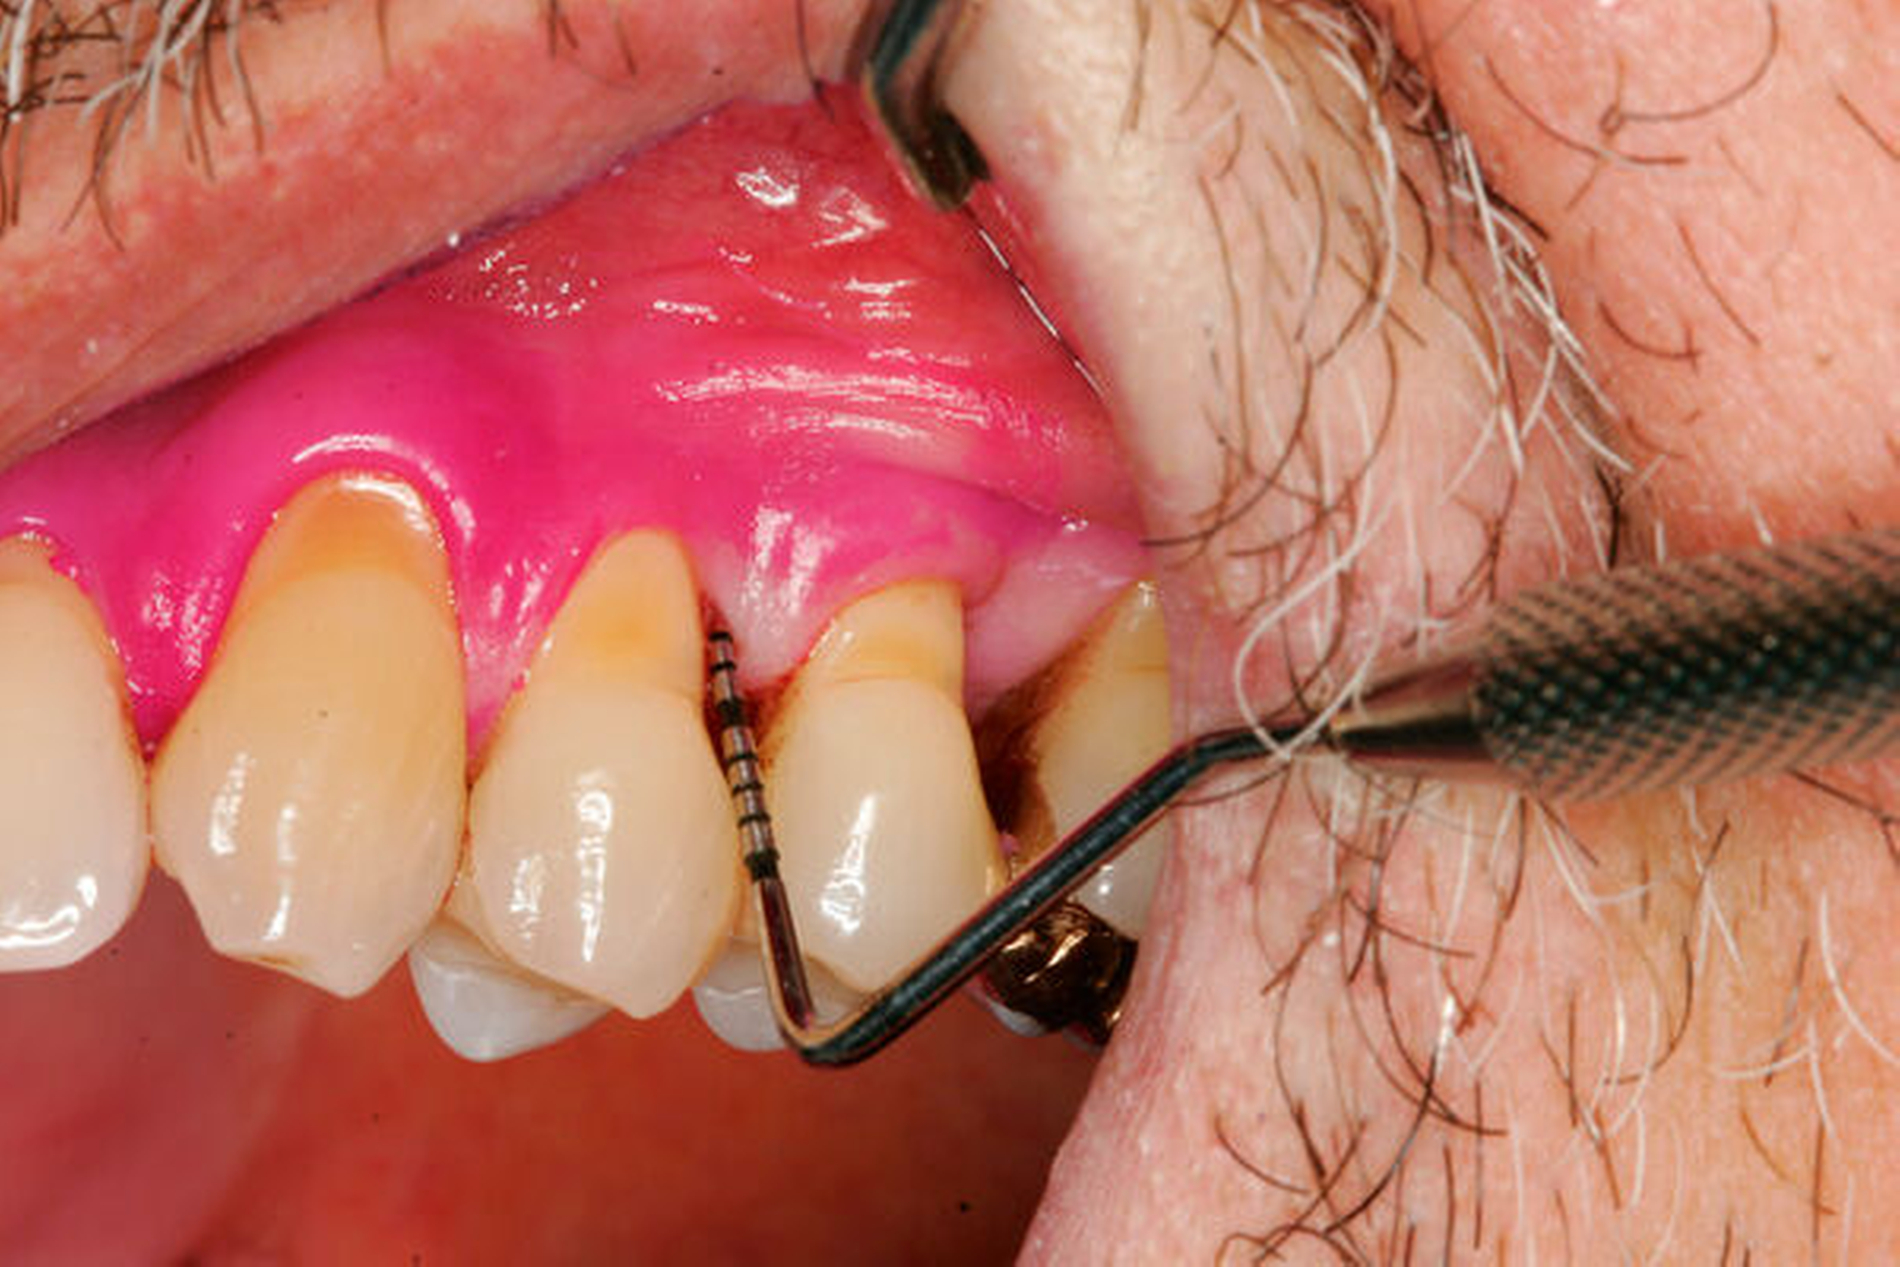

Werden verschiedene Zugangslappentechniken wie Instrumentierung unter Sicht mit Lappenbildung (Open Flap Debridement, OFD), Lappen mit paramarginaler Inzision (modified Widman Flap, MWF, Abbildungen 1 und 2), und Papillenerhaltungslappen (Abbildung 3) als konservative parodontalchirurgische Interventionen ohne signifikanten Weich- und Hartgewebsverlust hinsichtlich der Reduktion der TST verglichen, so bestehen kaum Unterschiede. MWF und OFD wurden in drei randomisierten klinischen Studien verglichen und nur eine davon hatte eine höhere Taschensondierungstiefenreduktion durch den MWF zum Ergebnis [Sanz-Sanchez et al., 2020].

Diese Fragestellung in der Leitlinie widmet sich dem Vergleich der Ergebnisse nach Lappenoperation mittels Zugangslappen (Abbildung 3), also Lappenbildung ohne gezielten Gewebsverlust, und resektiver Parodontalchirurgie – mit gezieltem Gewebsverlust, jedoch ohne zusätzliche Materialien zur parodontalen Regeneration [Polak et al., 2020]. Dabei werden alle chirurgischen Verfahren mit Resttaschen ab 5 mm nach vorheriger subgingivaler Instrumentierung verglichen. Bei der Betrachtung werden MWF (Abbildung 1), Excisional New Attachment Procedure (ENAP) in der Gruppe der Zugangslappen geführt. Die Gruppe der resektiven Parodontalchirurgie besteht aus auch zum Teil älteren Verfahren mit deutlicher Veränderung der Gingiva- und der Knochenkontur.